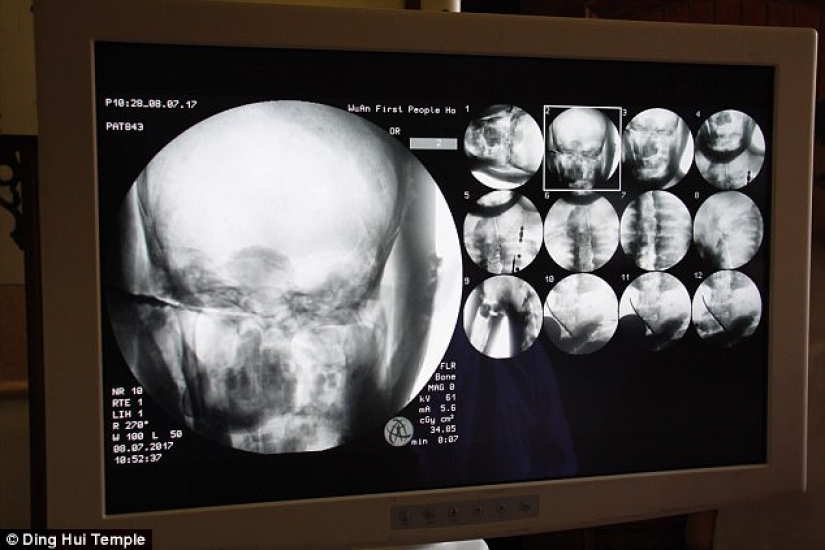

By Pictolic https://mail.pictolic.com/article/a-thousand-year-old-mummy-of-a-buddhist-monk-has-a-brain-and-skeleton-preserved-in-perfect-condition.htmlThe mummified body of a thousand-year-old Buddhist monk still has the bones and brain intact. This was revealed by a CT scan.

The discovery was made after the gilded remains of Master Ci Xian underwent a medical check at the Dinghui Temple in northern China.

The CT scan was performed on July 8. People were shocked when the doctors said that Ci Xian's skeleton and brain were in perfect condition. "We can see that his bones are as healthy as a normal person's. The upper jaw, upper teeth, ribs, spine, and all joints are perfectly preserved. This is incredible, " said Dr. Wu Yongqing.